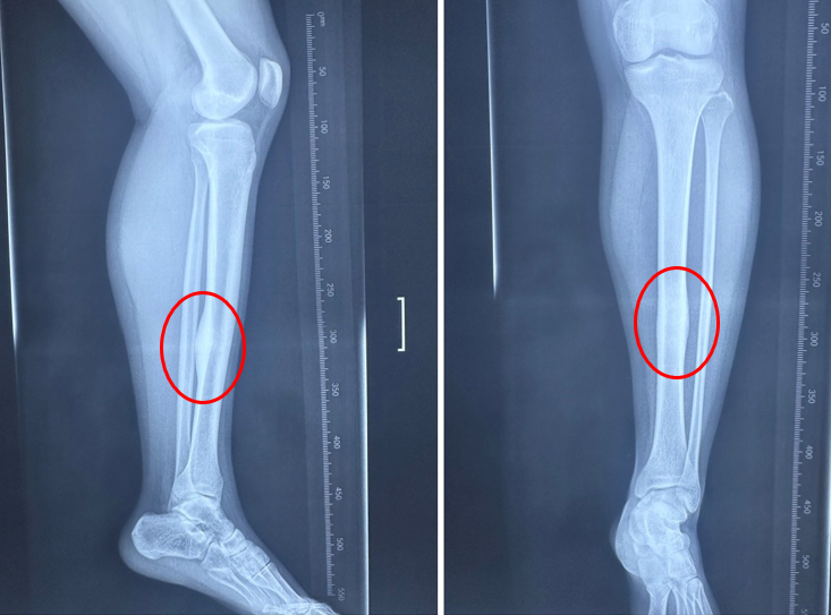

男性,17岁,因“左小腿疼痛10月余”就诊,患者10月前无明显诱因开始出现间歇性疼痛不适,夜间疼痛明显,口服塞来昔布可以缓解,逐渐加重。于当地医院就诊,行胫骨X线、CT及MRI检查,诊断为骨样骨瘤,当地医生无法确定,遂介绍至我院就诊。术前考虑患者为皮质型骨样骨瘤,瘤巢刺激骨皮质,胫骨内侧骨皮质增厚伴瘤巢形成,疼痛较为明显,但局部骨质太硬,单纯射频消融可能无法奏效,热量无法传导,导致消融范围失效,遂考虑采用导航下行左侧胫骨病灶超声骨刀磨除术的策略,采用水木天蓬超声骨刀铣刀头搭载Suretack连接S8导航系统。术后第二天患者自诉原有夜间疼痛有缓解,术后一个月基本感觉不到原来的疼痛。术后复查CT可见骨内明显的磨除隧道。

图6:术前左侧胫骨中下段影像检查提示骨皮质增厚

图8:术中导航及超声骨刀磨除

图9:术后复查CT见超声骨刀磨除的隧道